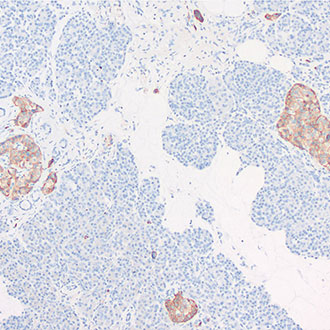

Synaptophysin

Synaptophysin -